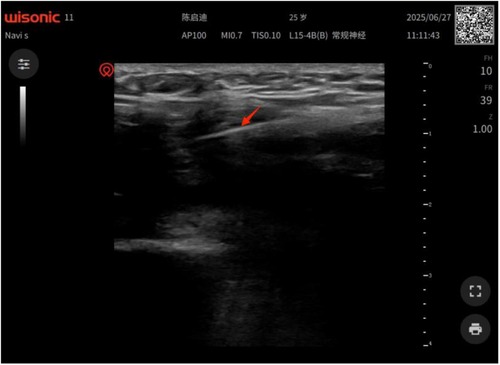

Patients with end-stage hemophilia often require total knee arthroplasty (TKA); however, the incidence of postoperative joint adhesions in these patients is significantly higher than that in the general population. Furthermore, due to their impaired coagulation function, the bleeding risk associated with traditional open adhesiolysis is also higher in this patient cohort than in the general population, and conservative rehabilitation therapy yields suboptimal outcomes. Thus, there is an urgent clinical need for a safe and effective intervention regimen. This study reports a 25-year-old male patient with severe hemophilia A (factor Ⅷdeficiency), whose baseline factor Ⅷactivity was 0.8%. Severe knee joint adhesions occurred 3 months after TKA, manifested as difficulty in walking, sitting, and standing. A combined treatment regimen of "perioperative precise coagulation factor replacement + ultrasound-guided acupotomy release under anesthesia + graded manual release" was adopted for the intervention of post-TKA adhesions in patients with severe hemophilia A. The results showed that this combined regimen may represent a feasible minimally invasive option for the clinical management of post-TKA adhesions in severe hemophilia A patients.